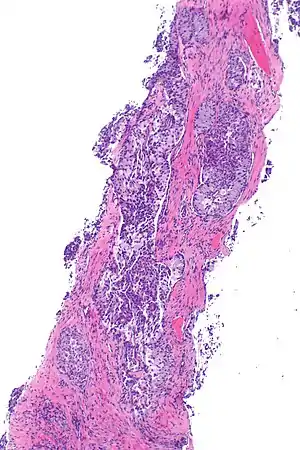

| Micrograph showing ALK positive lung adenocarcinoma. H&E stain. | |